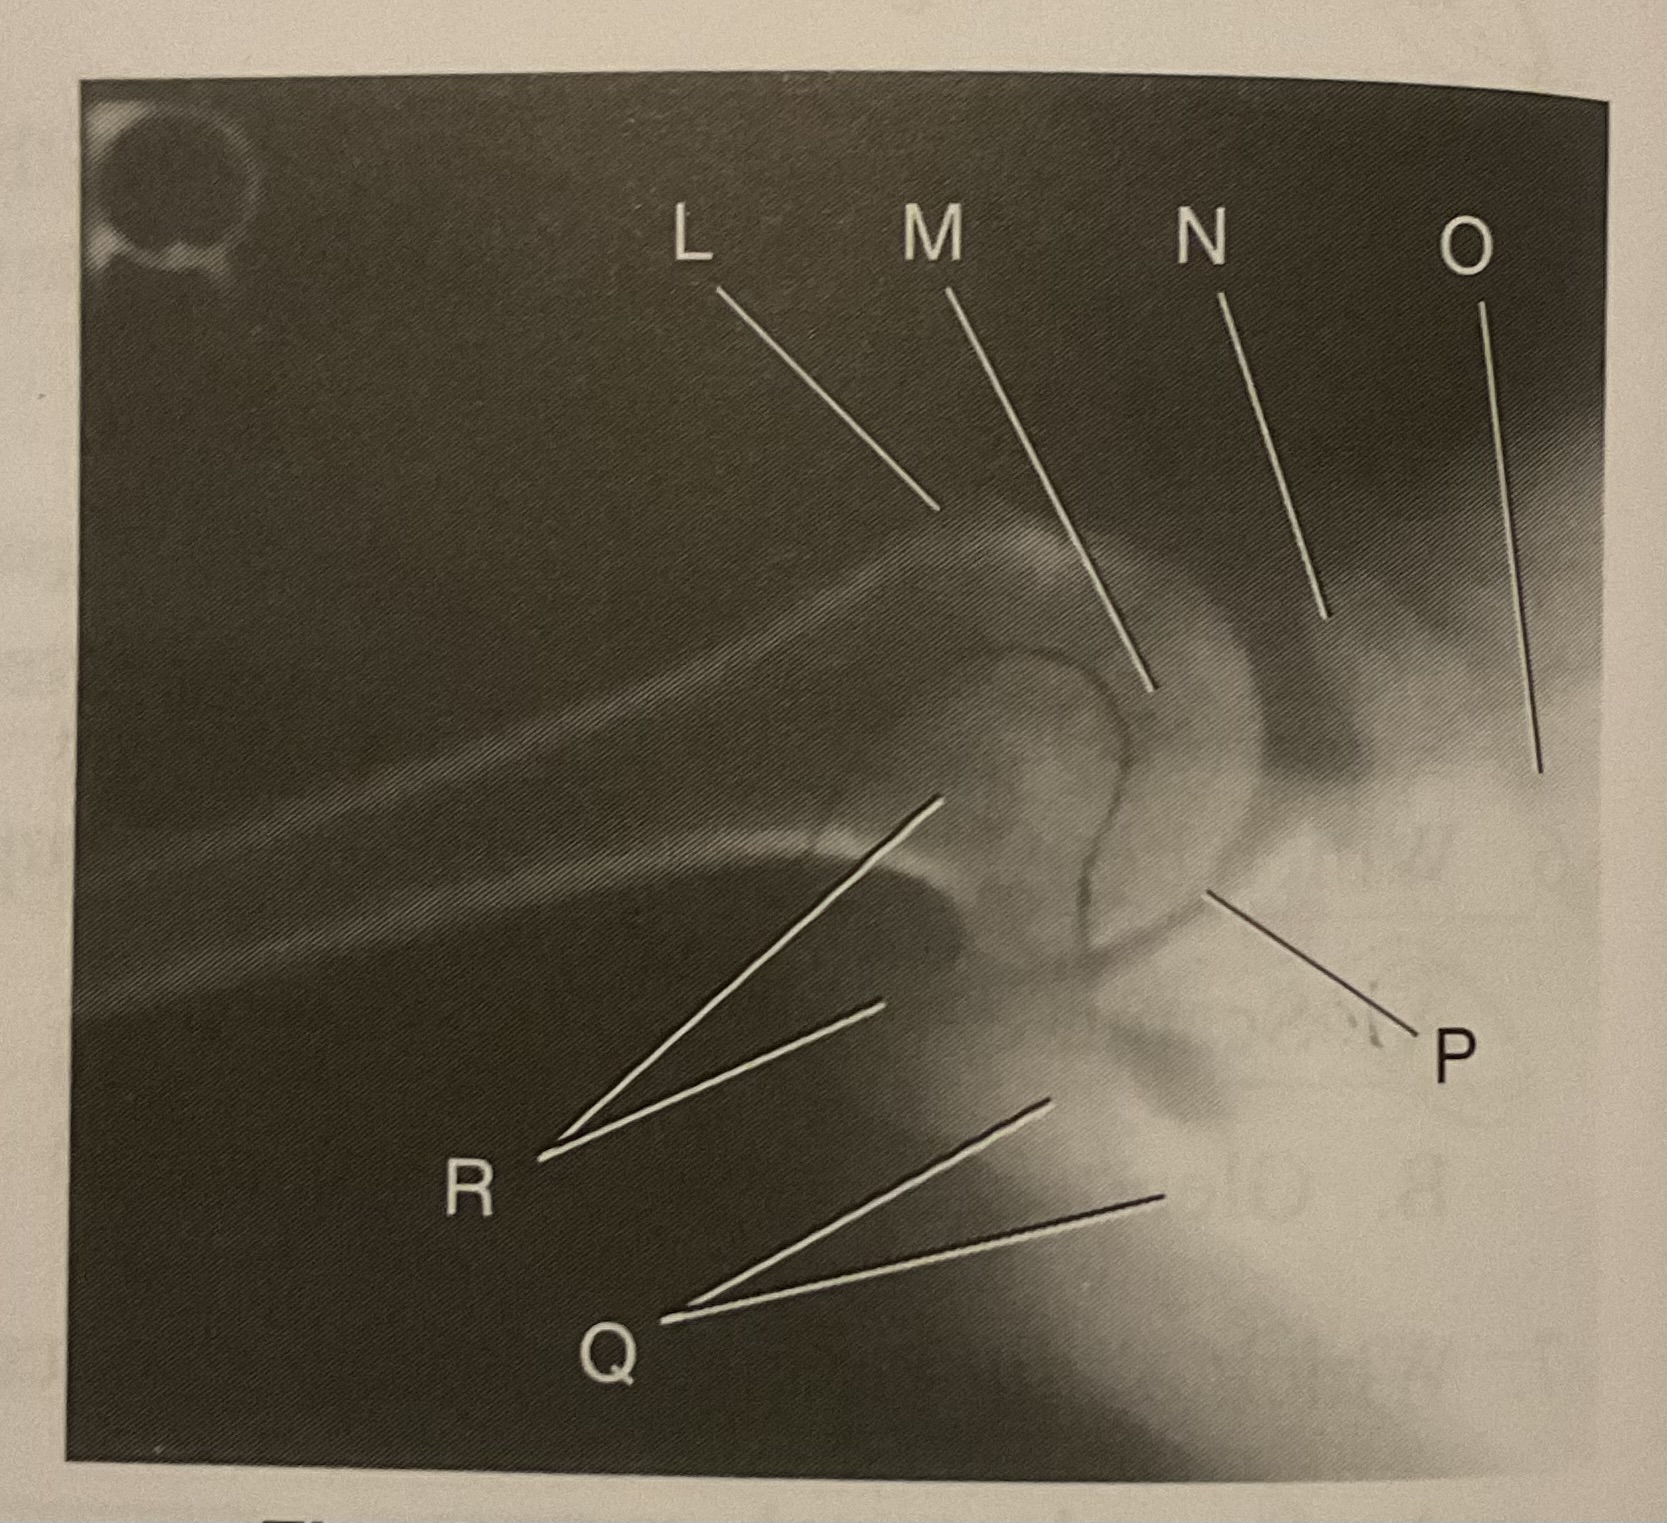

What AP projection does this image represent?

External

L?

Lesser tubercle

M?

Head of humerus

N?

Coracoid process

O?

Clavicle or lateral extremity of clavicle

P?

Glenoid cavity or Scapulohumeral joint

Q?

Spine of scapula

R?

Acromion of scapula

What is the correct term and method for the projection seen in this image?

Inferosuperior axial projection